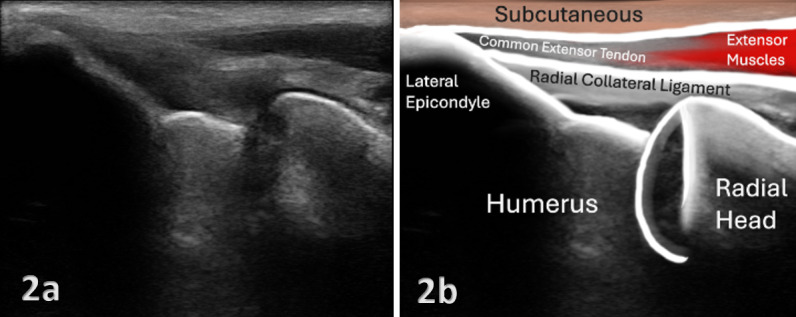

Recordatorio breve de cómo se ve el tendón extensor sano

El tendón extensor común sano muestra un patrón fibrilar hiperecoico bien organizado, con fibras paralelas y continuas. En la inserción sobre el epicóndilo, el tendón tiene un grosor que oscila aproximadamente entre 3 y 5 mm, aunque hay variabilidad individual.

Justo en la zona de inserción, es habitual ver una pequeña zona levemente hipoecoica en la cara profunda del tendón, donde el extensor radial corto del carpo se relaciona con la articulación. Esto es normal y se relaciona con la estructura fibrocartilaginosa de esa zona. No lo confundas con patología: si el patrón fibrilar se conserva y no hay otros signos, estás ante un tendón sano.